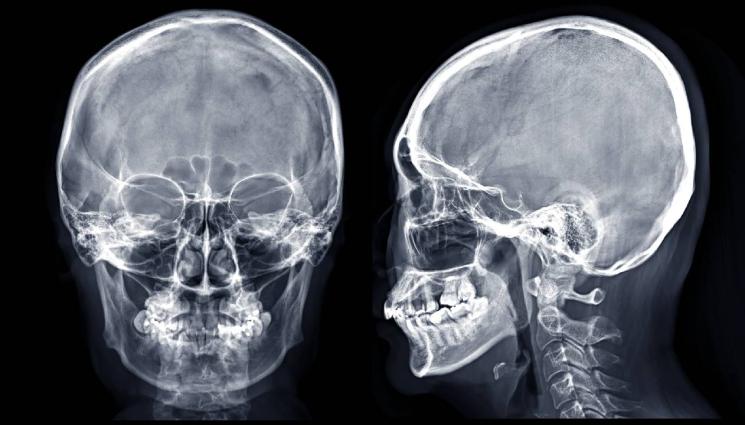

За да постигне този резултат, изследователският екип е имплантирал микроелектроди в моторния кортекс (частта от мозъка, отговорна за говора, бел.ред.), за да регистрира невронните сигнали. Участниците в проучването бяха с тежка парализа, причинена от амиотрофична латерална склероза (ALS, известна още като болестта на Шарко) или вследствие на инсулт. Изследователите са ги помолили да се опитат да говорят или да си представят, че произнасят поредица от думи. И двете действия активирали припокриващи се области на мозъка и предизвикали сходни видове мозъчна активност.